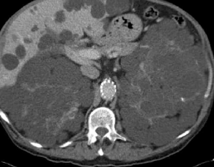

Liver after resection of the infected cyst. Presence of hemostatic Surgicel on the raw surface (Courtesy Dr. V. Penopoulos)